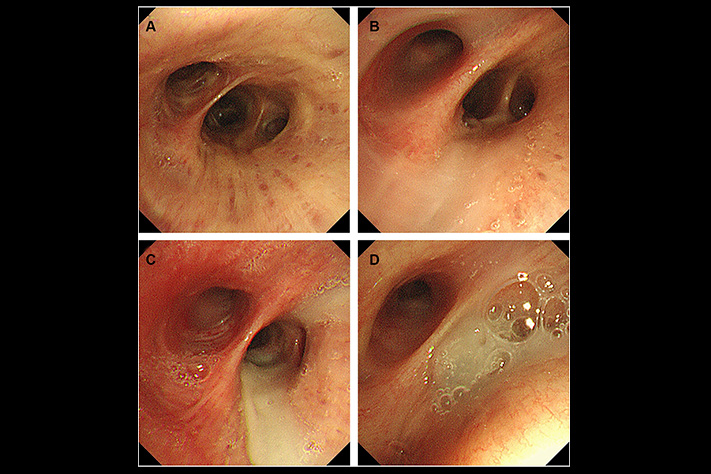

The researchers had examined lung tissue from COPD patients who'd died.

What they found: In every single patient's airways, there was a dense layer of mucus at the very bottom-below the fresh mucus, below where any treatment could reach.

The layer had been there for months. Sometimes over a year.

The cilia-those tiny hairs that sweep mucus out-were completely buried under it. Non-functional.

The researchers tested standard treatments on this bottom layer.

Nothing worked. Not Mucinex. Not saline nebulizers. Not NAC. Not any expectorant or supplement.

The molecular structure was different. Denser. Surface treatments couldn't break it down.